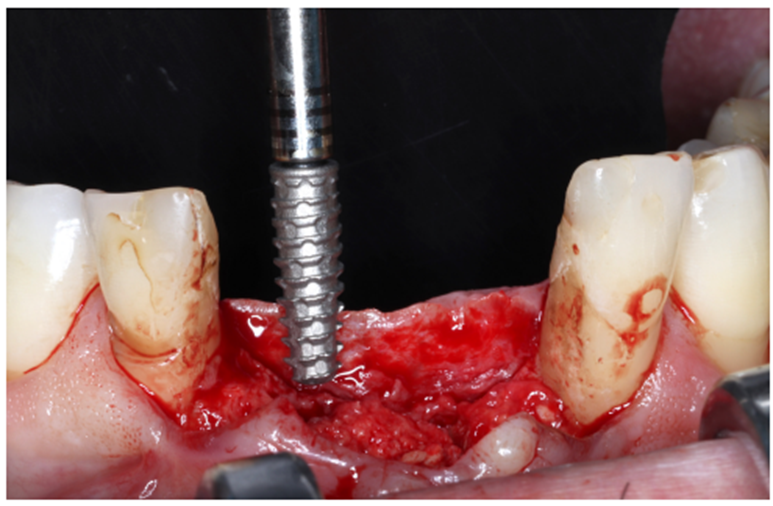

Após oito meses, foi realizada nova tomografia para análise do ganho ósseo vertical, assim como o planejamento dos implantes do tipo Cone Morse Maestro – Implacil De Bortoli (Figura 7). Foram planejados e realizados dois implantes 3.5 X 11 mm Cone Morse Maestro após remoção da membrana Cytoplast, devido ao ótimo ganho ósseo vertical, evidenciando sucesso da técnica de regeneração óssea guiada (Figuras 8, 9 e 10). Após a espera de apenas três meses devido a qualidade do implante e suas câmaras de cicatrização, o que possibilita uma osseointegração precoce, foram realizadas duas metalocerâmicas parafusadas sobre pilares Ideale reto, da Implacil De Bortoli, devido ao ótimo posicionamento tridimensional (Figuras 11 e 12).